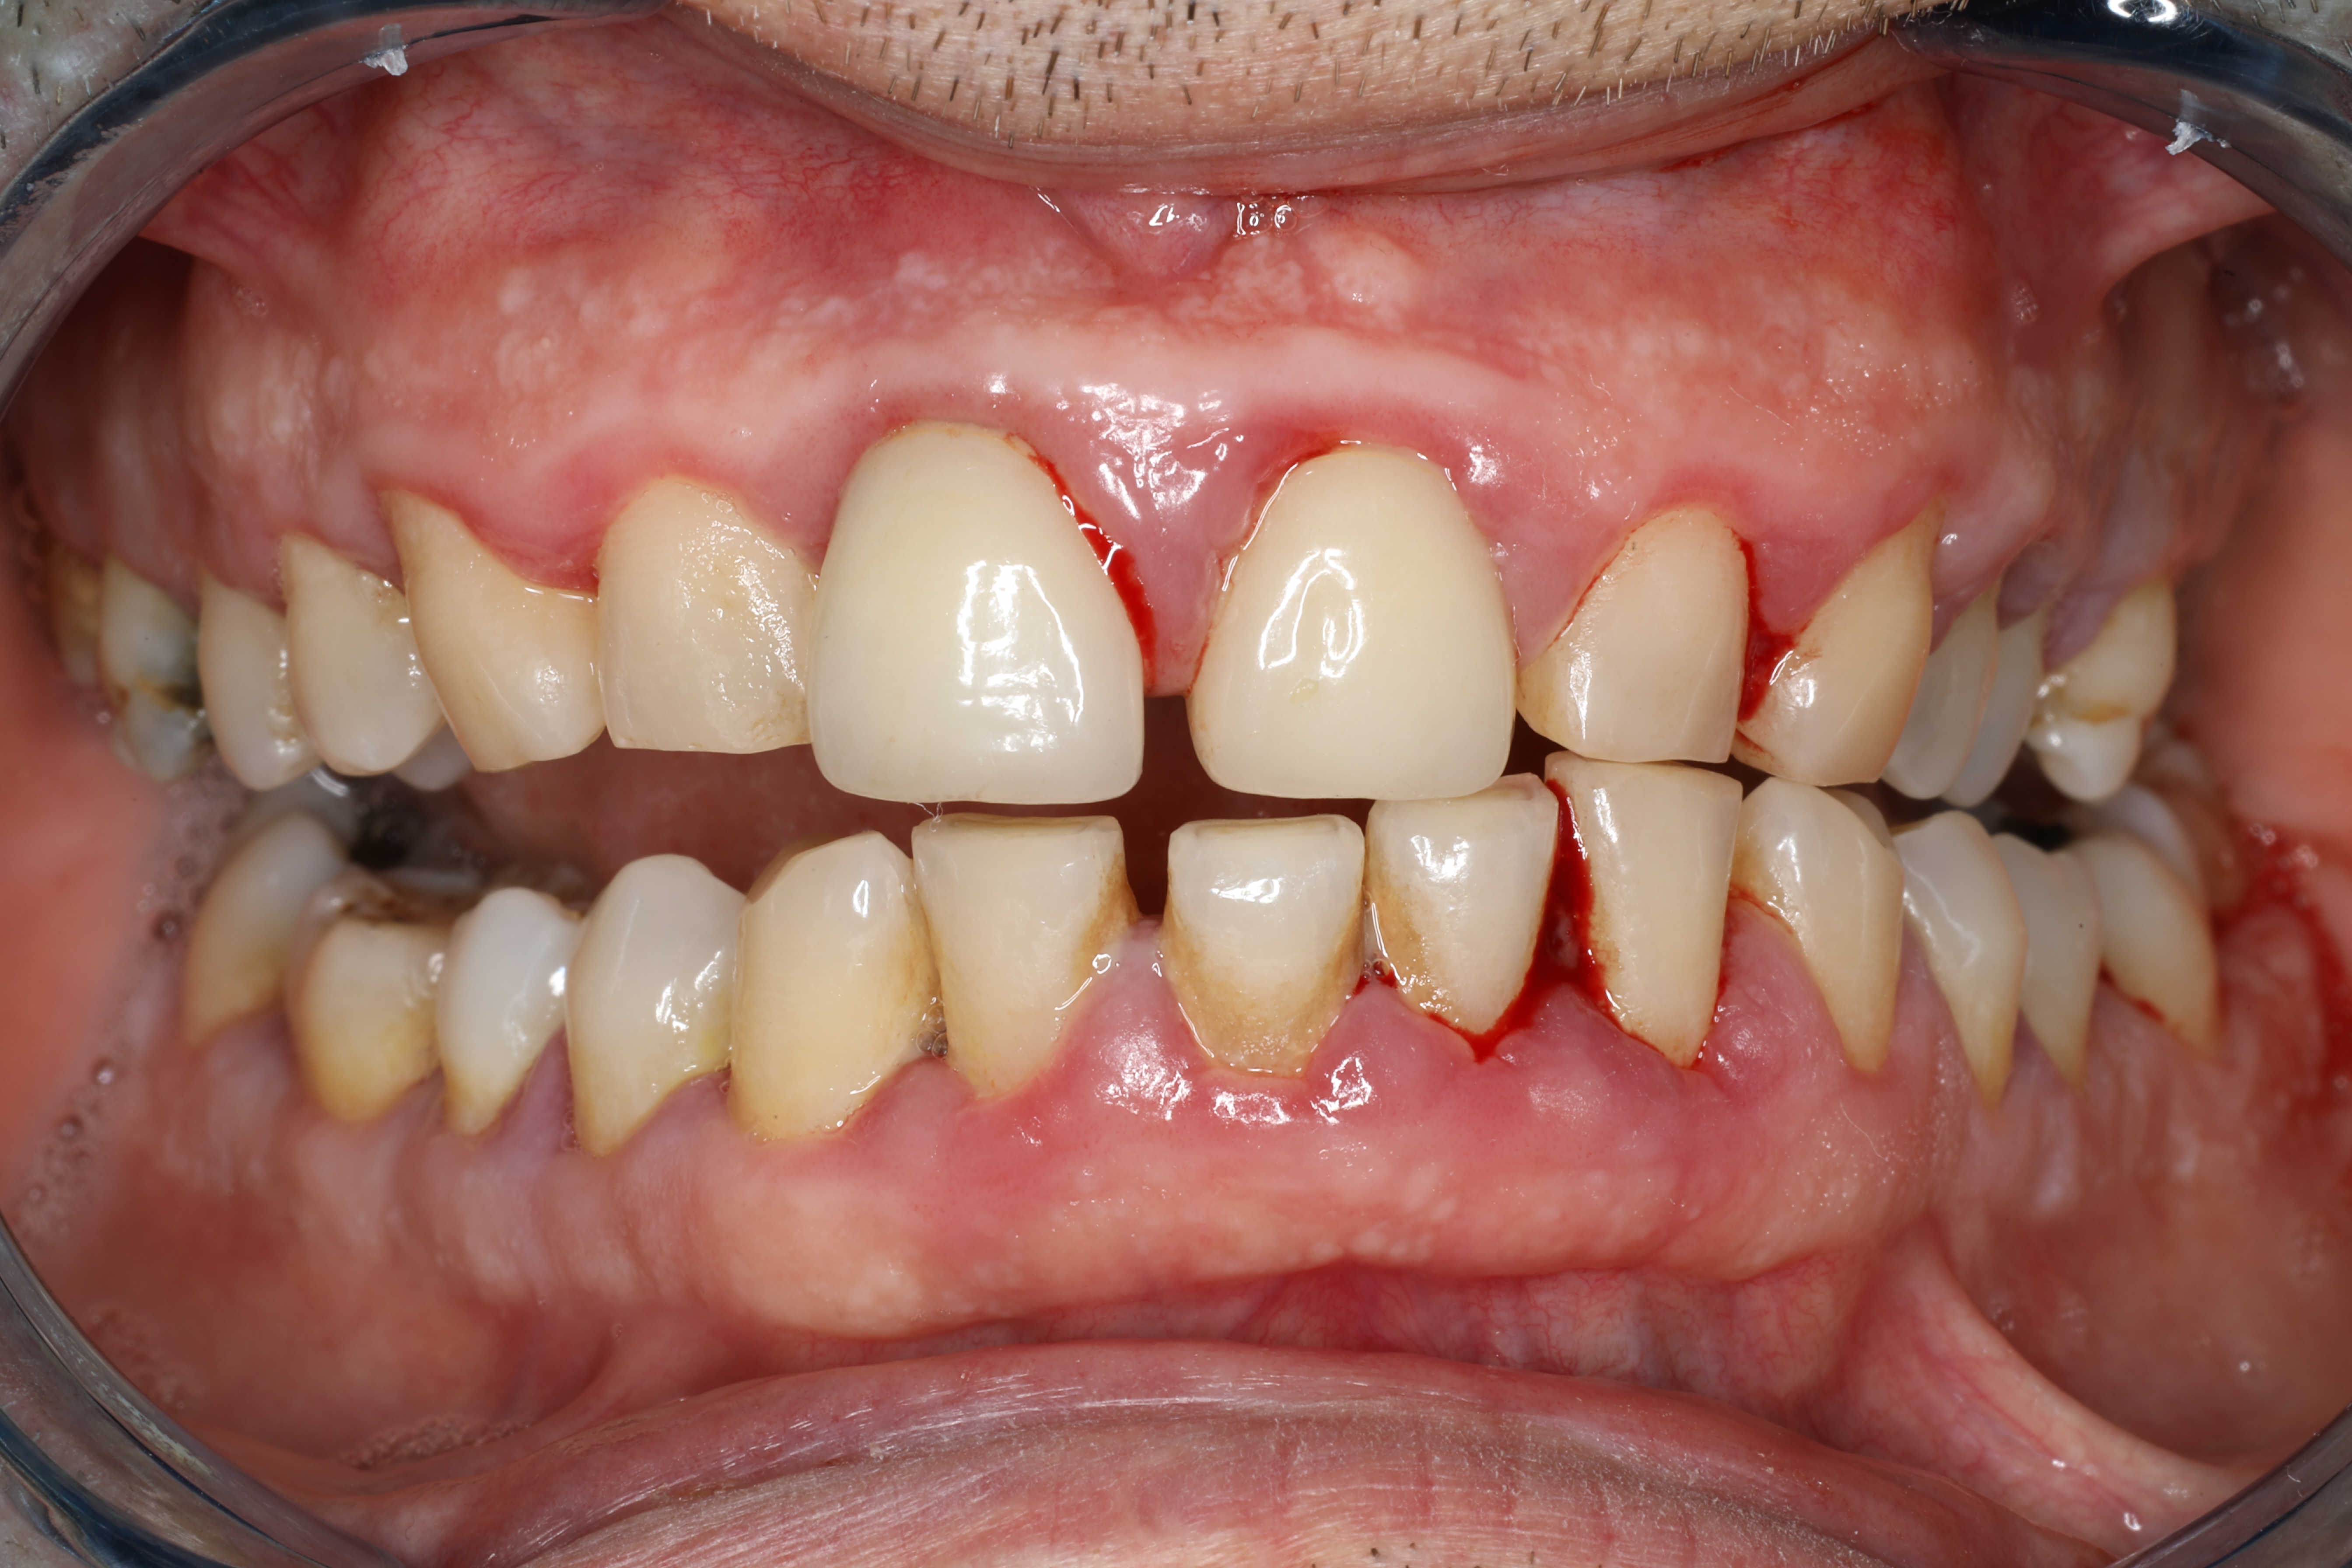

20. "Gum disease. Even dentists tin place this arsenic mean aging."

Juan Francisco Garcia Leon / Getty Images